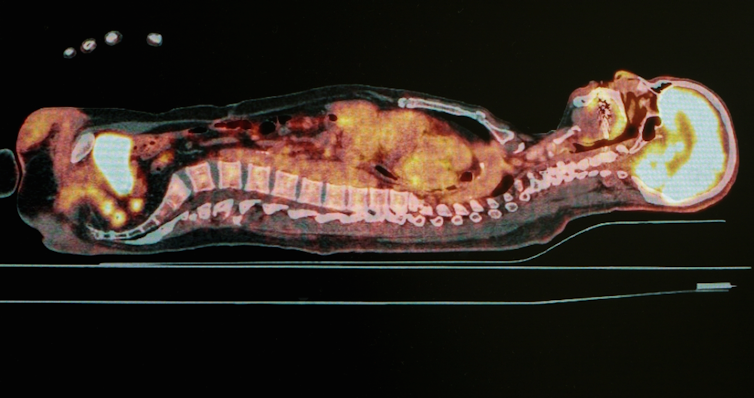

Positron emission tomography (PET)

The imaging techniques used with x-rays, CT and MRI, are mostly designed to observe structural information – this includes the arrangement of anatomy and the location of disease or injuries. PET imaging is a unique imaging process, as it can identify and image functional information such as metabolic (the converting of energy) or chemical processes of internal body organs.

To do this, radioactive substances need to be injected into patients and these are chemically bonded to compounds used by our organs (such as glucose) or molecules that bind to specific receptors or specific types of cells (such as proteins).

These radioactive substances emit gamma rays (another form of ionizing radiation). From their location within the body, the gamma rays pass through tissue and exit the body where they are detected by a PET scanner containing a gamma camera while the patient is lying still.

The PET scanner detects the gamma rays, converts their intensity or strength into an electrical signal and then reconstructs an image based on this intensity. The detectors are arranged around a patient’s body so the originating location of the gamma rays within the patient can be calculated using mathematical processes.

PET imaging is excellent for identifying the activity of tumours within organs that cannot be structurally identified with other imaging techniques.

Even though the thought of being injected with radioactive material may sound dangerous, it actually isn’t. Imaging techniques similar to this have been around for many decades and PET imaging techniques are performed nearly everyday in major hospitals across Australia.